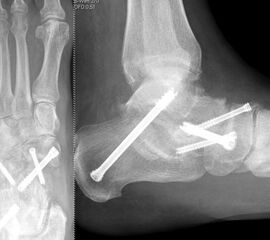

Die Operation erfolgt meist über einen medialen Zugang. Nach Entknorpeln der  Gelenkflächen und Anfrischen des subchondralen Knochens kann die Arthrodese mit Schrauben oder Plattensystem erfolgen (Abb. 5). Bei Fehlstellungen muss diese vor der Osteosynthese korrigiert und das Talonavikulargelenk reponiert werden. Pseuarthrosen werden hier zwischen 8-25% angegeben 3223.

Die isolierte Arthrose der Bona Jäger Gelenkreihe (navikulocuneiforme Gelenk) ist selten und oft posttraumatisch. Meistens geht die navikulocuneiforme Arthrose mit einem schmerzhaften Pes planovalgus einher 2425. Letztlich werden die betroffenen Gelenkflächen angefrischt und mittels verschiedener Implantat-Möglichkeiten (s.o.) fusioniert. Bei gleichzeitiger Plattfußfehlstellung sollte diese ebenfalls adressiert werden 26 (Abb. 4). Ziel ist die Arthrodese in anatomischer Stellung der Gelenke.